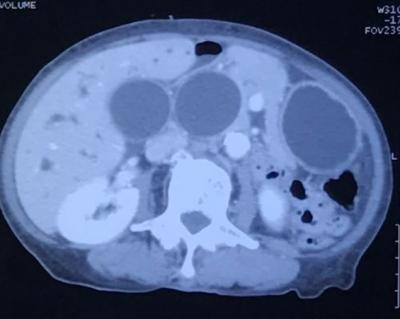

Biliary & Gastric Dilation

Figure 1: Computed tomography showing 3 homogenously enhanced lesions on axial view